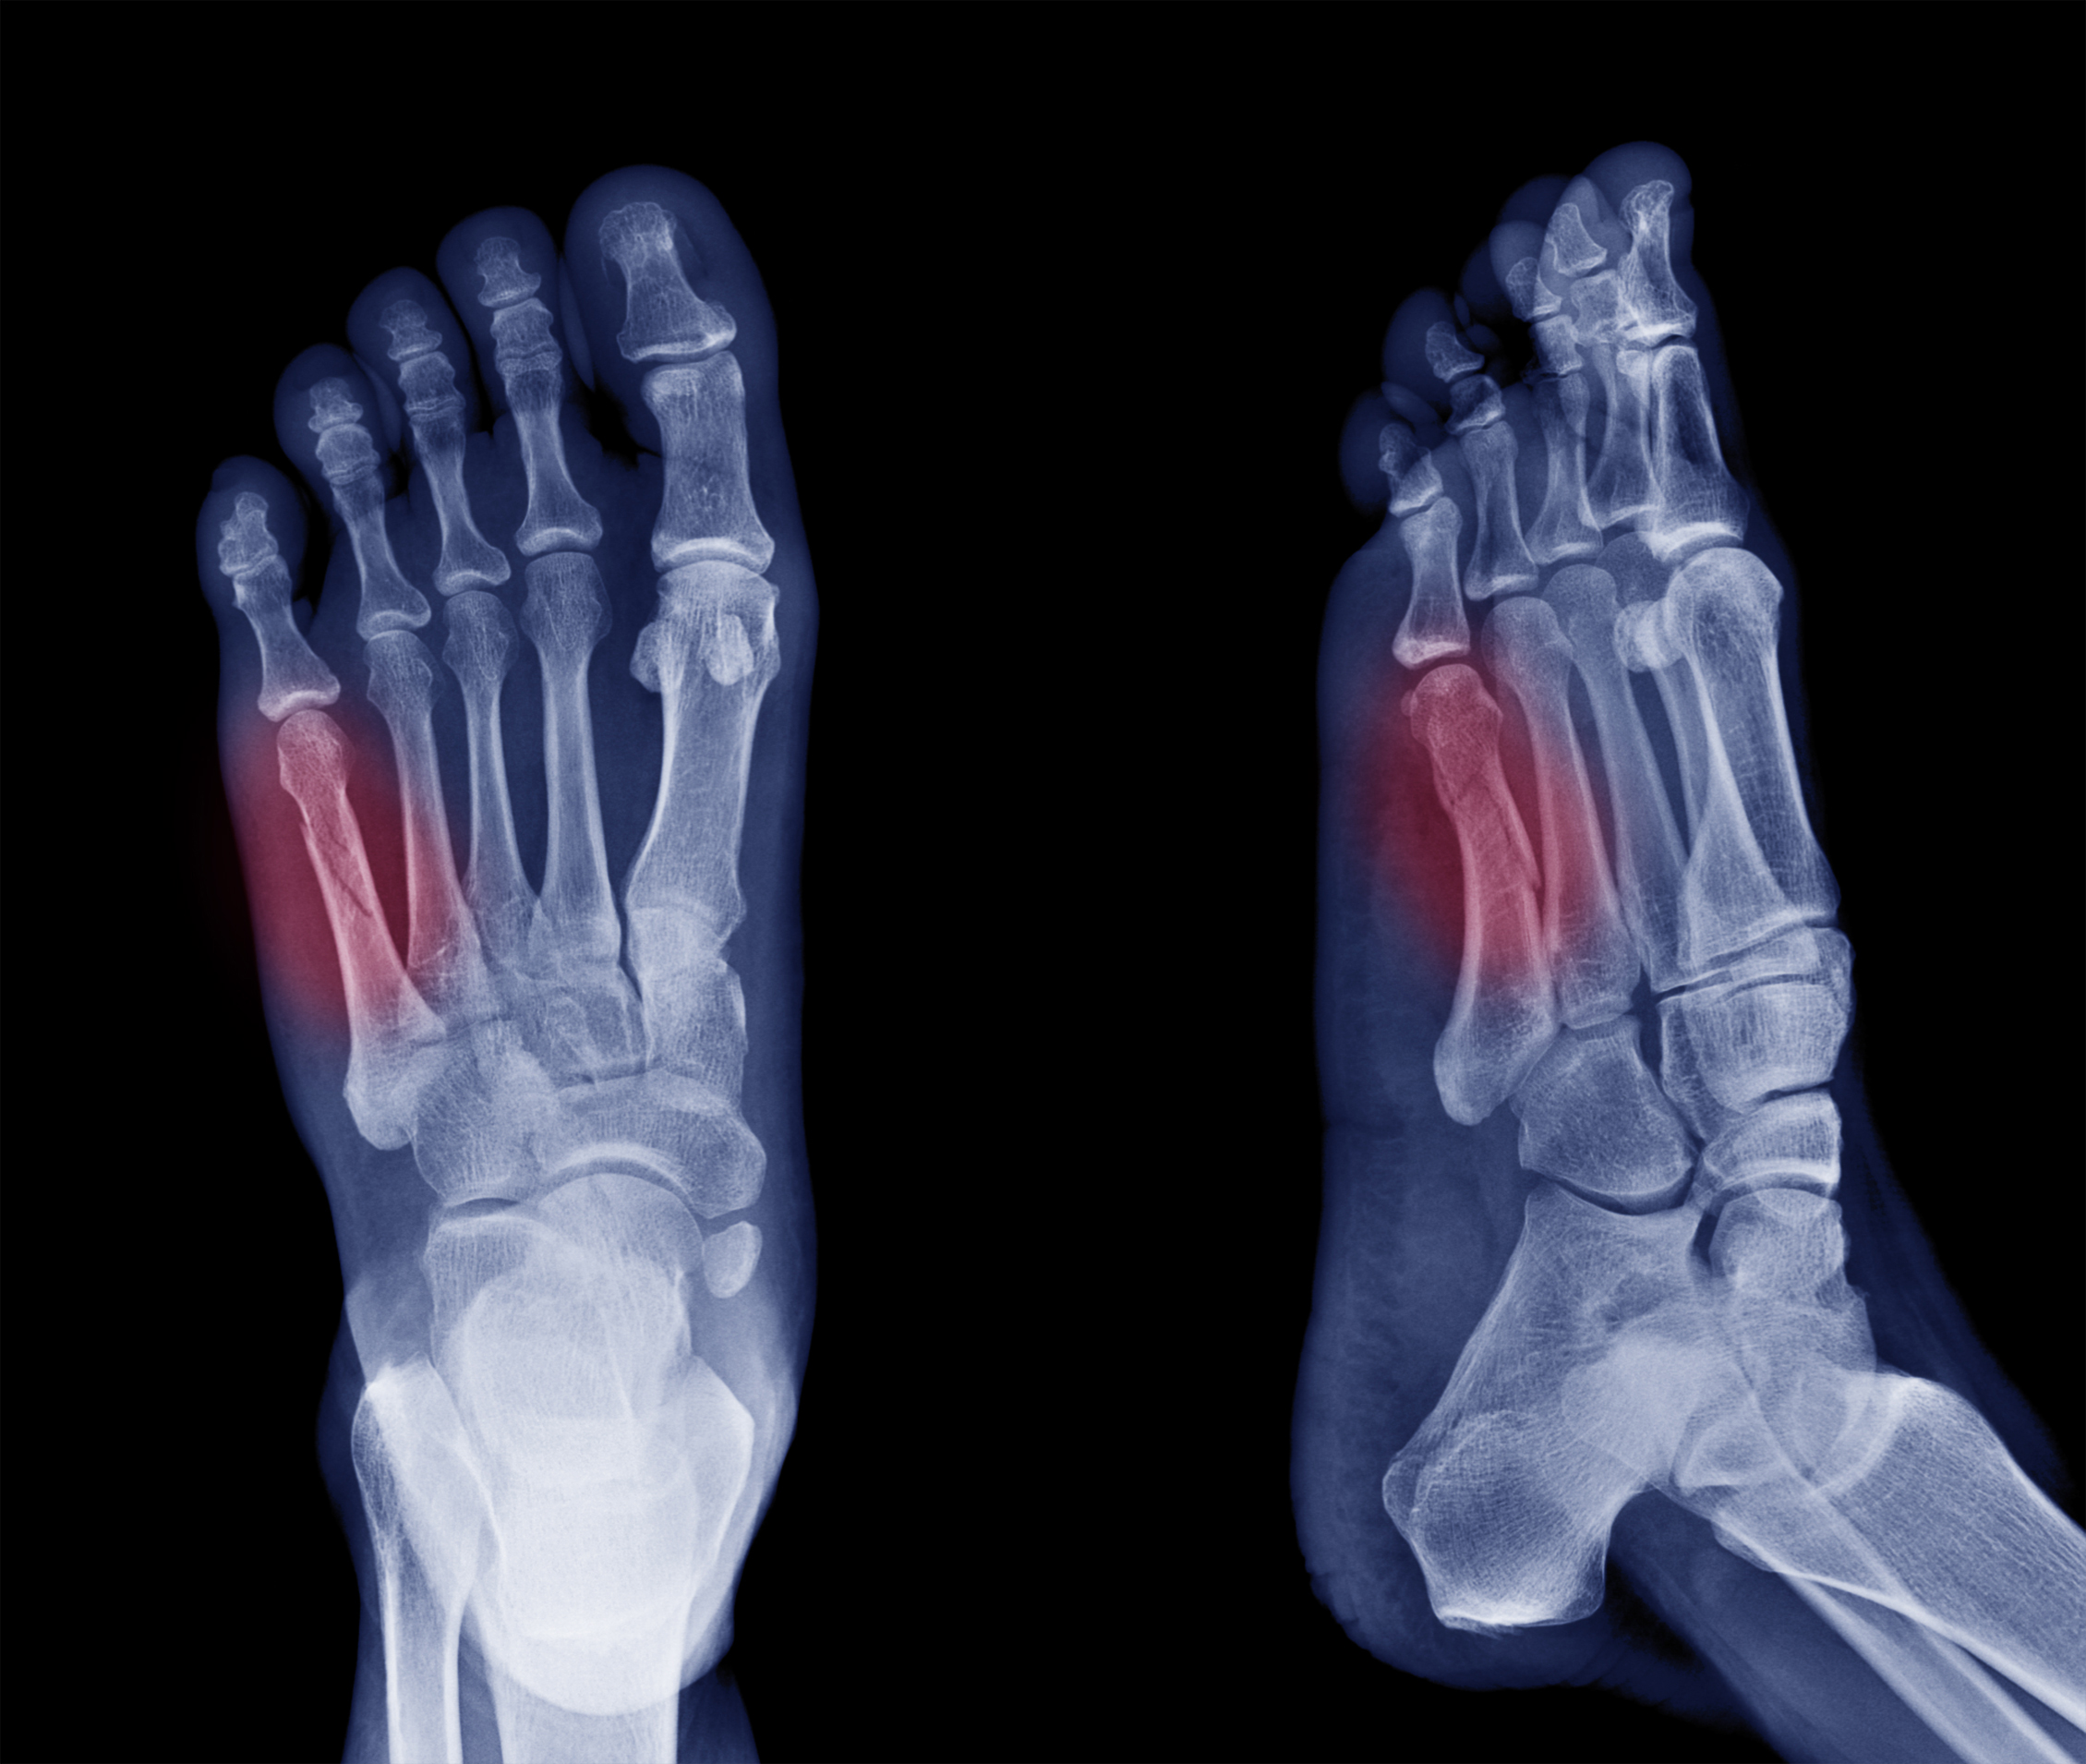

X-ray image of diabetic patient with amputation.